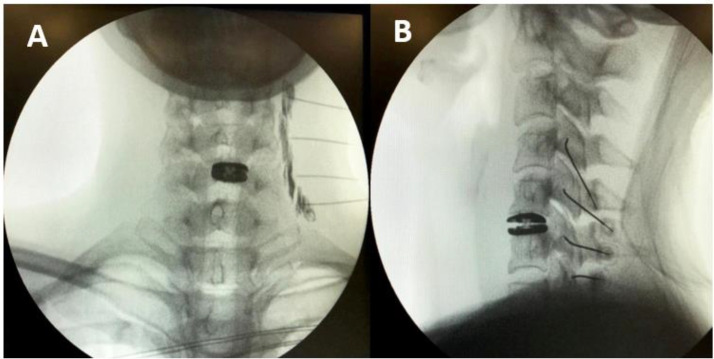

IPSIS Cervical RFN Technique Details

The IPSIS evidence-based technique for cervical medial branch radiofrequency neurotomy (CMBRFN) has specific hallmarks:

Cannula and Electrode Selection

• Large-gauge cannulae (16G or 18G) with a 10 mm sharp, bent active tip are preferred

Cervical Target Zones

• Because medial branches assume variable positions relative to their articular pillars, there is no single electrode placement point — instead, there is a zone of likely nerve location that must be covered

• Typical levels (C3-6): The C5 medial branch is consistently at the mid-pillar; C3, C4, and C6 branches are progressively higher. Two parallel large-gauge cannula placements in the middle and upper aspects of the lateral pillar are typically needed

• C5 level: May only need one cannula placement if using 16G

• C7 medial branch: Three lesion locations needed (C7 SAP apex, SAP base, and root of the transverse process). The narrow C7 SAP requires a near-sagittal or slightly (5 degrees) ipsilateral oblique trajectory to avoid passing into the C6-7 neural foramen

Critical Safety — Depth Control

• The cannula tip must NEVER advance ventral to the anterior margin of the articular pillar (C3-6) or the SAP (C7/TON)

• Foraminal oblique views provide essential auxiliary imaging to verify the cannula is safely posterior to the cervical foramen and exiting nerve/vertebral artery

Cervical Lesion Parameters

• Temperature: 80-85 degrees C for at least 90 seconds per lesion

• Multiple tightly overlapping lesions are made to cover the entire zone of nerve probability

• Cervical: target a ZONE of nerve probability, not a single point — variable nerve positions require multiple lesion placements (IPSIS)

• Cervical safety: cannula tip must NEVER advance beyond the anterior margin of the articular pillar; use foraminal oblique views to confirm (IPSIS)